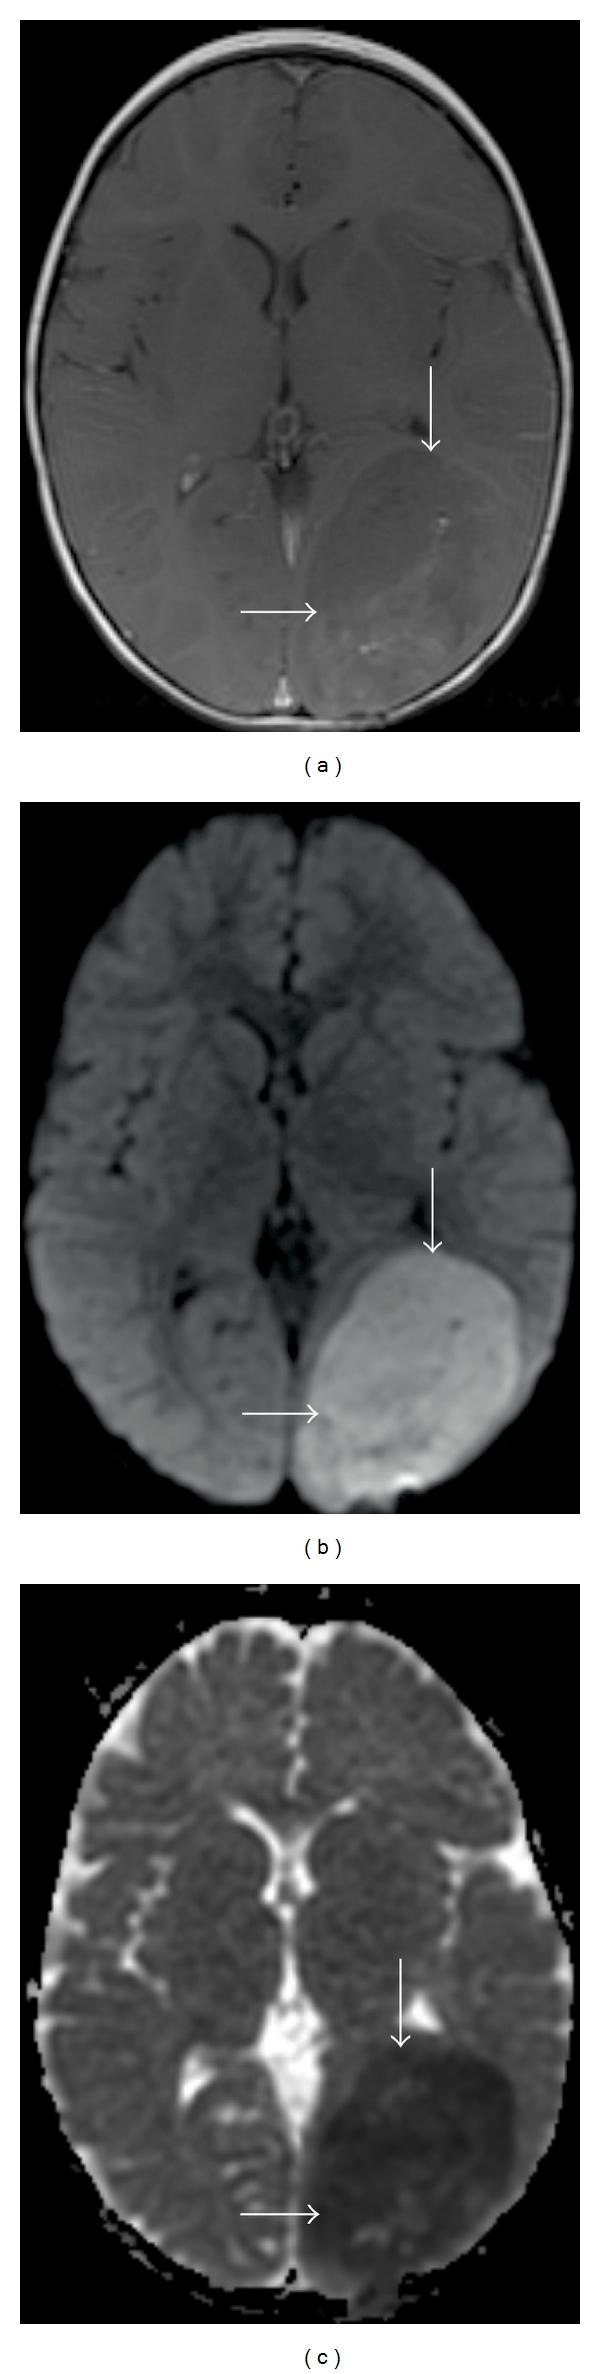

Diffusion MR Imaging of the Brain in Patients with Cancer.

Over the last several years, there has been significant advancement in the molecular characterization of intracranial diseases, particularly cerebral neoplasms. While nuclear medicine technology, including PET/CT, has been at the foreground of exploration, new MR imaging techniques, specifically diffusion-weighted and diffusion tensor imaging, have shown interesting applications towards advancing our understanding of cancer involving the brain. In this paper, we review the fundamentals and basic physics of these techniques, and their applications to patient care for both general diagnostic use and in answering specific questions in selection of patients in terms of expected response to treatment.

在过去几年中,颅内疾病,尤其是脑肿瘤的分子特征研究取得了重大进展。虽然包括PET/CT在内的核医学技术一直处于探索前沿,但新的磁共振成像技术,特别是扩散加权成像和扩散张量成像,在推进我们对脑部癌症的理解方面显示出了有趣的应用。在本文中,我们回顾了这些技术的基本原理和基础物理学,以及它们在患者护理中的应用,包括一般诊断用途以及在回答关于患者对治疗预期反应的特定选择问题方面的应用。